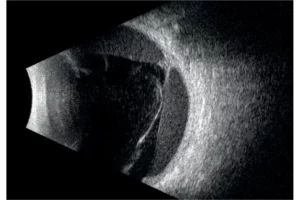

Quantel Medical heeft een sprong voorwaarts gemaakt met de nieuwe technologie met 5 ringen op een 20 MHz-sonde. Het principe is om om en om ultrasone geluidsgolven uit te zenden via 5 concentrische transducers in dezelfde sonde. Deze technologie:

Het volledige oog is nu zichtbaar met een uitstekend detailniveau.

- Verhoogde scherptediepte waardoor het gehele oog zichtbaar is.

- Hoge resolutie die het mogelijk maakt om van het voorste gedeelte van het glasvocht tot aan de wand te zien.